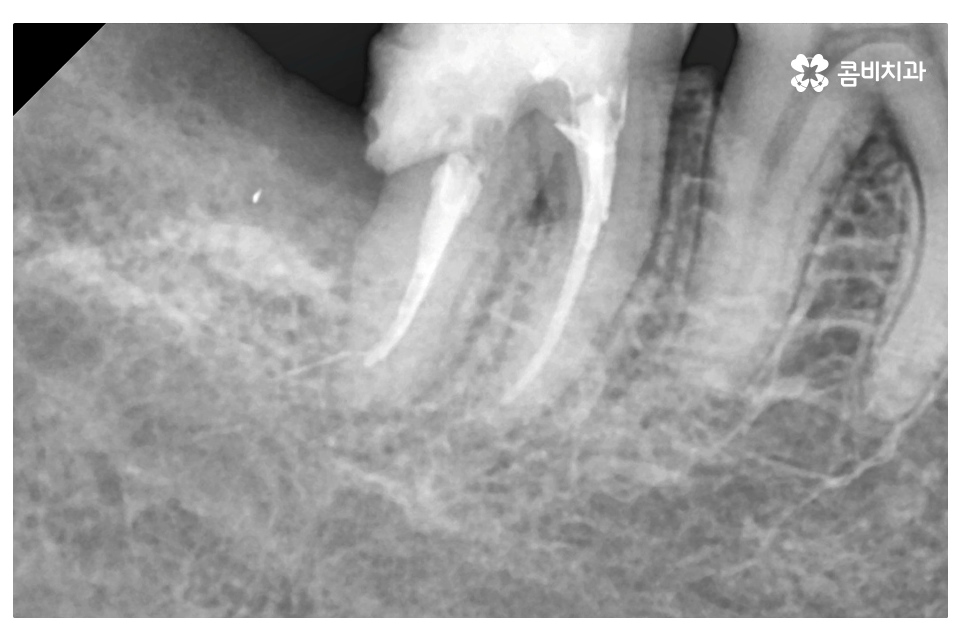

위처럼 누운 사랑니의 경우 단지 사랑니의 발치 만으로 끝나는 것이 아니라

주변 치아, 평생 지켜야 할 어금니 손상을 유발할 수 있기 때문에

자연치아를 잘 보존하기 위해서는 경우에 따라서 미리 사랑니 발치를 하는 것이

구강질환의 예방에 중요하다고 할 수 있어요.

특히 누운 사랑니의 경우 발치에 대한 경험이 많고 실력을 갖춘

의료진에게 치료를 받는 것이 좋으며 그와 함께 시술 후 회복도

생각해야 하기 때문에 사랑니 발치에 유리한 시기에 치과를 찾을 필요가 있어요.

엑스레이 사진에서 보시는 것처럼 사랑니로 인해 어금니 옆 부분에

충치가 발생되었고 사랑니 발치 후 어금니 신경치료를 하여

자연치아의 손상이 커진 케이스라고 할 수 있는데요